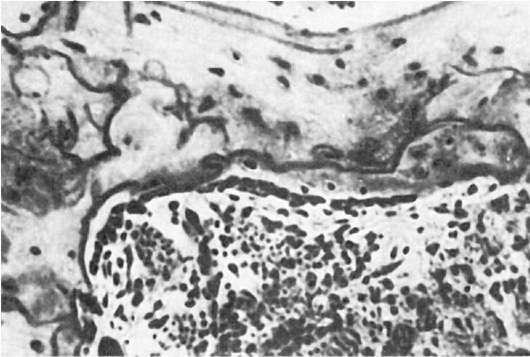

Микроскопическая картина чрезвычайно своеобразна: патологическое костеобразование происходит на протяжении всей кости, масса костного вещества резко увеличена, само вещество кости беспорядочно нагромождено во внутренних отделах костей (рис. 245). Костномозговые

Рис.

245. Остеопетроз. Беспорядочное нагромождение костных структур (по А.В. Русакову)

пространства заполнены беспорядочно расположенными слоистыми костными конгломератами или пластинчатой костью с дугообразными линиями склеивания; наряду с этим встречаются балки эмбриональной грубоволокнистой кости. Видны единичные участки продолжающегося костеобразования в виде скоплений остеобластов. Остеокласты единичны, признаки резорбции кости выражены незначительно. Архитектоника кости вследствие беспорядочного образования костных структур утрачивает свои функциональные характеристики, с чем, очевидно, связана ломкость костей при остеопетрозе. В зонах энхондрального окостенения резорбция хряща практически отсутствует. На основе хряща формируются своеобразные округлые островки из костных балок, которые постепенно превращаются в широкие балки.